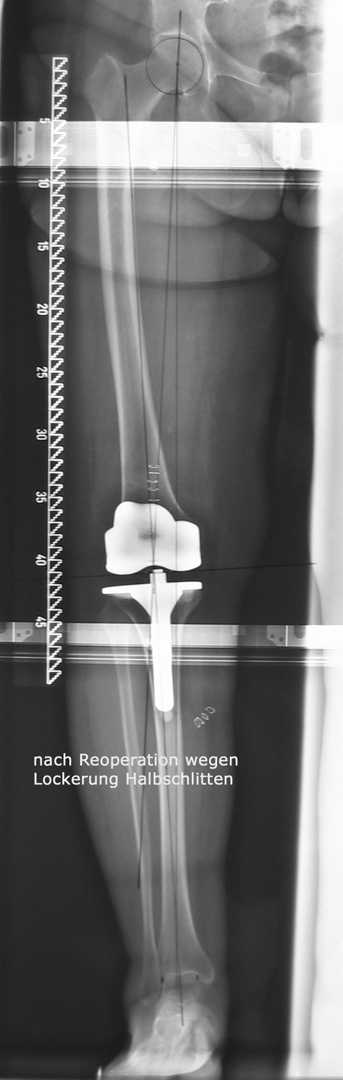

Welcher Typ einer Knieprothese für die Behandlung der Kniegelenksarthrose verwendet wird hängt neben dem Patientenalter vorwiegend davon ab, welche Teile des Gelenks abgenützt sind. So können bei isolierten Abnützungen des inneren Gelenksteils sogenannte Schlittenprothesen ( linkes Bild) und bei Abnützungen des gesamten Gelenks Totalprothesen  (mittleres Bild) eingesetzt werden: In besonders schweren Fällen von Fehlstellung in Kombination mit fehlender oder unzureichender Bandstabilität werden auch immer wieder sogenannte achsegeführte oder gekoppelte Prothesenmodelle (rechtes Bild) eingesetzt.

Reoperationen von gelockerten Gelenksprothesen

Reoperationen von gelockerten Gelenksprothesen sind anspruchsvolle operative Eingriffe , bei denen die Erfahrung des Operateurs und die Gabe zur richtigen Einschätzung der optimalen Versorgungsform von grosser Bedeutung ist. Reoperationen können dann erforderlich werden, wenn das Gefüge zwischen Knochen und Prothese aufgelockert wird – so kann eine Entzündung, ein vermehrter Abrieb der Prothesenteile, ein Bruch des die Prothese umgebenden Knochens aber auch Verletzungen der Weichteile eine Prothesenlockerung verursachen. Rasches Handeln ist dann angezeigt wenn der Patient über Schmerzen klagt, Röntgenuntersuchungen die Änderung der Prothesenposition

erkennen lassen oder Spezialuntersuchungen wie zum Beispiel eine Szintigraphie Hinweis auf eine Prothesenlockerung geben. Der operative Eingriff selbst ist für den Patienten belastend aber nur durch rasches Handeln kann die weitere Zerstörung von Knochen und Weichteilen verhindert werden.

Bild anklicken zum Vergrössern